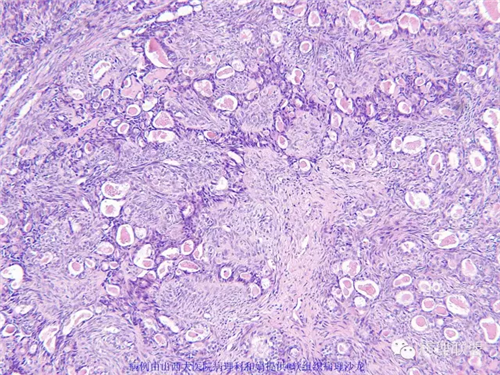

M,57岁,右膝关节外侧皮下肿物10余年,活动度好。

免疫组化结果阴性:S-100,SMA,Calponin,CD10,CD99,CD34,CEA,PHH3。

本例形态学上是非常典型的双相型滑膜肉瘤,滑膜肉瘤临床上大部分表现为生长缓慢的肿瘤。以青壮年多见,主要发生于四肢大关节附近,也可见于其他少见部位,如肺、肾等实质器官,形态学分为5种类型:单相纤维型、单相上皮型、双相型、低分化梭形细胞型和小细胞型。有文献报道个别患者有长达20年的病史。